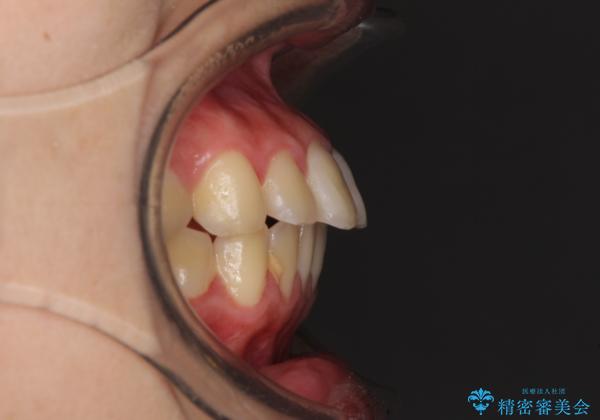

- 口元が出てるのが気になるとのことで来院されました。

歯のがたつきはあまりなかったのですが、口唇が閉じずらく、口元の突出感が確認できました。

上下左右の歯を1本ずつ抜歯して、そのスペースを利用して口元を引っ込める計画としました。